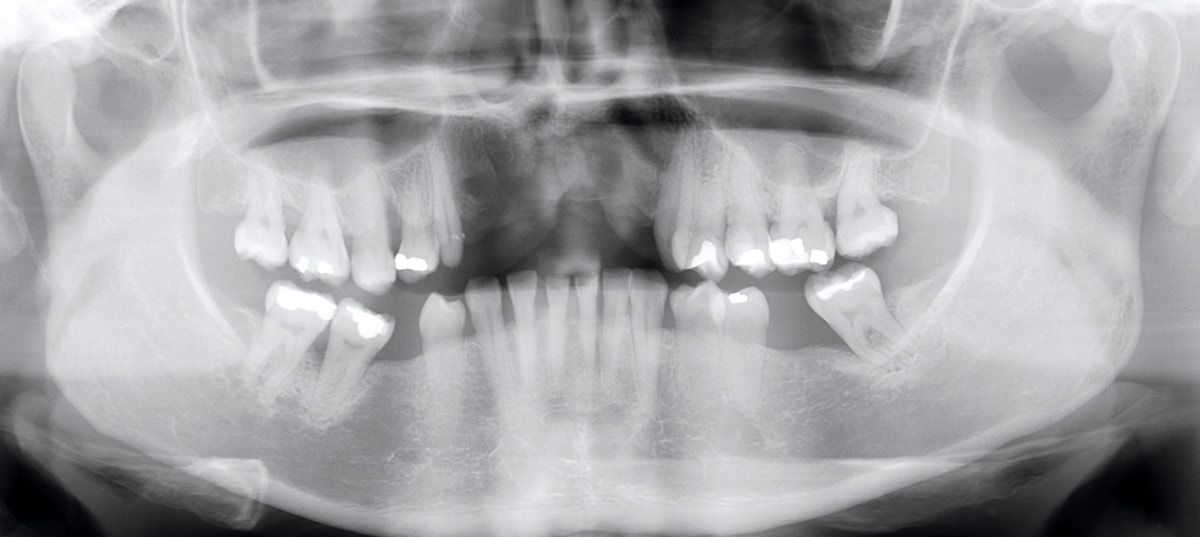

4/17 - X-ray scan after extraction of failing implantsRestoration of all four incisors with maxgraft® bonebuilder - Dr. Dr. Dr. O. Blume